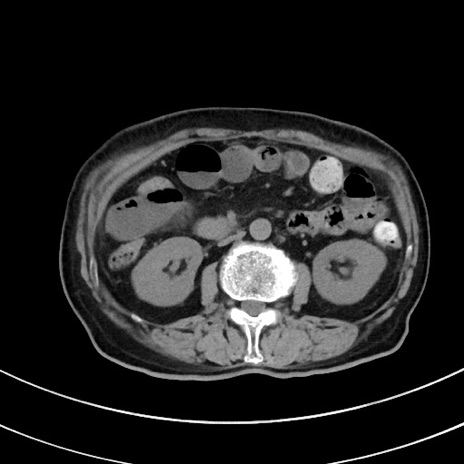

症例33(横断像)

【症例】70歳代 女性

【主訴】心窩部痛

【現病歴】延髄病変の精査・加療にて神経内科入院中。本日より心窩部痛あり。

【身体所見】右下腹部を中心に圧痛と反跳痛あり。

【データ】WBC 10900、CRP 0.02